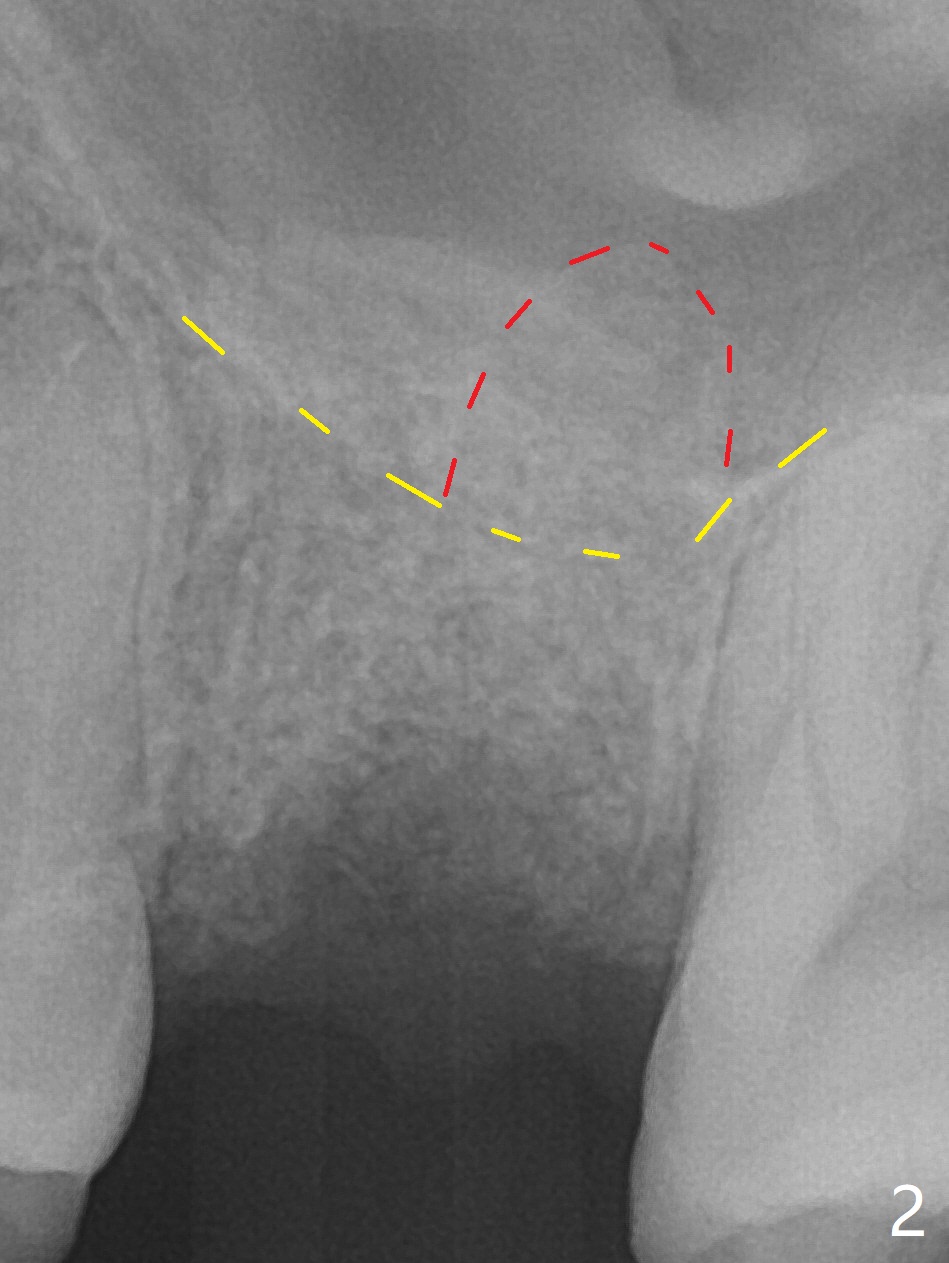

A 38-year-old woman requests extraction of the tooth #14 with mesiobuccal fistula (Fig.1). After extraction, the buccal plate is found to be defective. Bone graft enters the apex of the palatal root (Fig.2 red dashed line) so that the bone height increases by 6 mm (Fig.3). Following placement of collagen plug and suturing, acrylic dressing is applied to the undercuts of the neighboring teeth for retention.